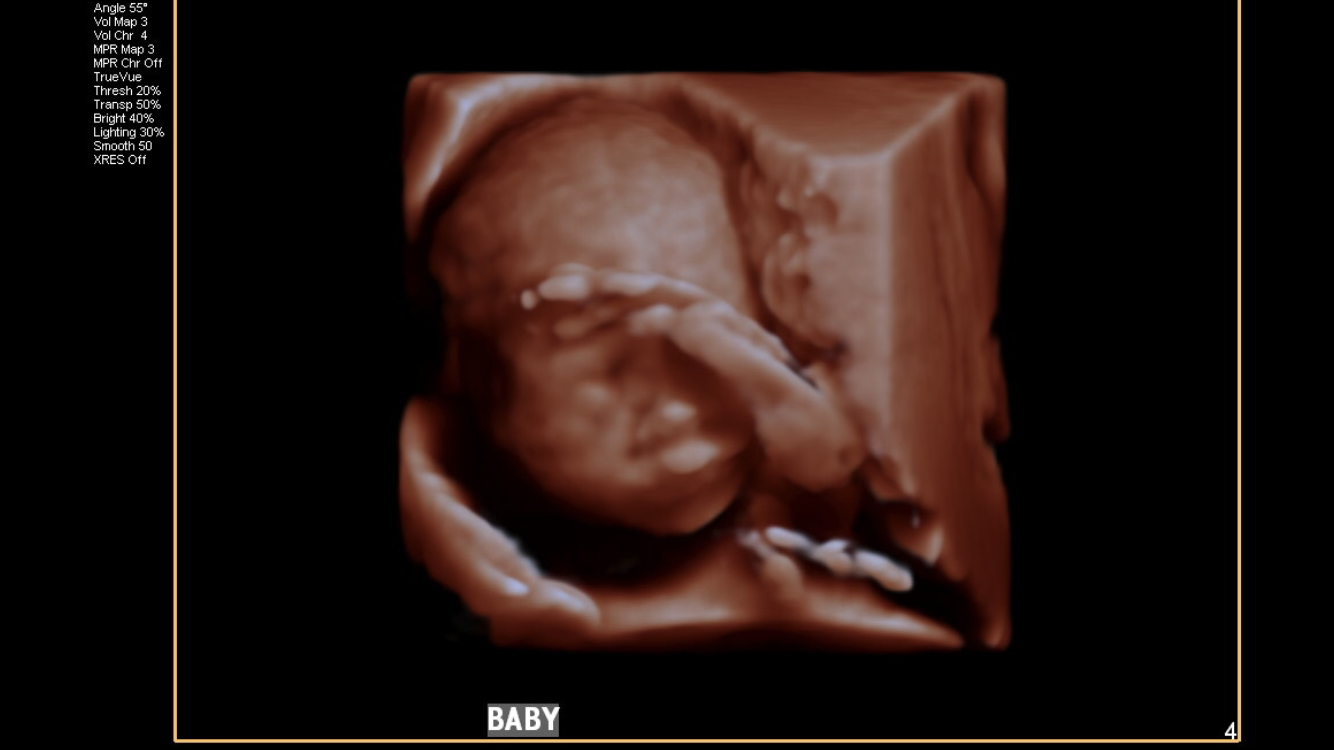

20 week scan today with MFM plus fetal echocardiogram, and no issues to report! Baby boy #2 ... And he's smiling! 99th percentile just like his brother.

Anatomy scan today! It was so much fun to see baby moving around in there doing some crazy acrobatics! And it is BOY #3 for this Mama